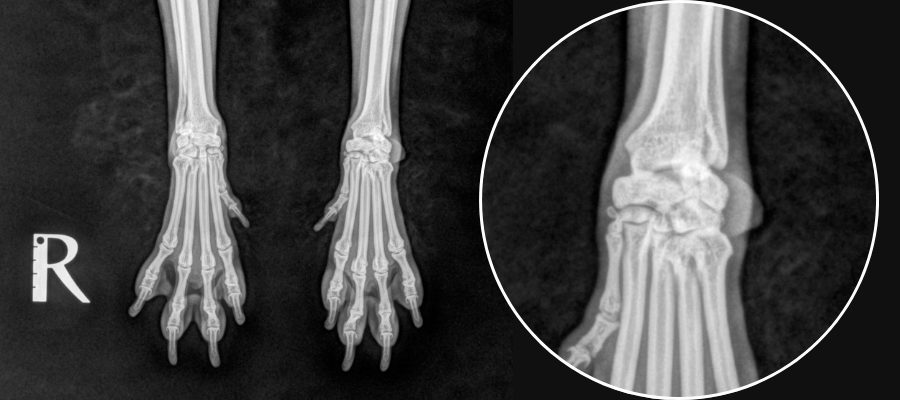

<手根関節のレントゲン>

【健常】

自己免疫の異常によって自分の関節を攻撃してしまう疾患です。免疫介在性関節炎に含まれ、多数ある免疫介在性関節炎のうち、びらん性関節炎に分類されます。びらん性とはレントゲン検査で骨びらん(骨の虫食い様の不連続像)が認められることを指します。 主な症状は、関節の腫れ、足を痛がるなどの症状です。日によって、または時間によって痛がる足が変わることがあります。重症例では関節が壊れることにより、かかとや手首がベタっと地面についてしまいます(いわゆるベタ足)。また、関節症状以外にも発熱、食欲不振などの全身症状も見られることがあります。